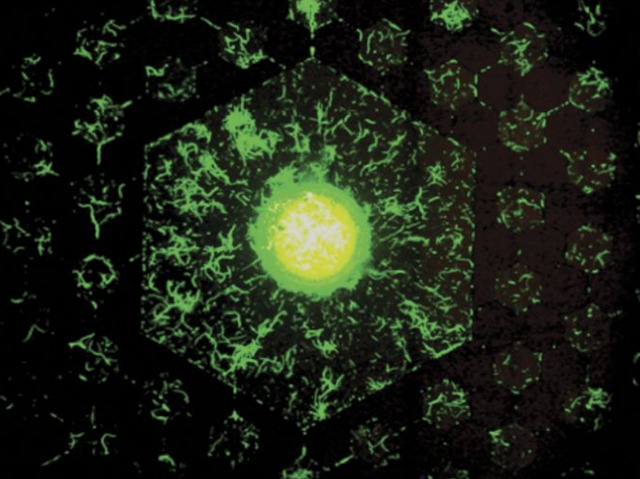

La capacitat dels bacteris infecciosos per a desenvolupar ràpidament resistència als antibiòtics és un problema important. Algunes soques poden suportar tots els antibiòtics que tenim, i estem lluitant per a obtindre noves versions. Una raó és que no entenem completament com els microbis es fan impermeables. Però ara els investigadors estan revelant alguns dels passos involucrats. Quan Escherichia coli s'exposa a l'antibiòtic ciprofloxacina, canvia de la seua forma usual de vareta a la de filaments allargats (imatge), cadascun dels quals conté múltiples cromosomes. En aquest cas, s’indueixen mutacions que eventualment produïxen cromosomes mutants amb resistència a la ciprofloxacina. Finalment, el filament es dividix repetidament per la punta, formant cèl·lules descendents resistents a l'antibiòtic. No està clar com les cèl·lules saben quan han de deixar de retocar l'ADN i començar a dividir-se. Però pareix que la generació de múltiples cromosomes mutants als filaments és vital en el desenvolupament de la resistència als antibiòtics.